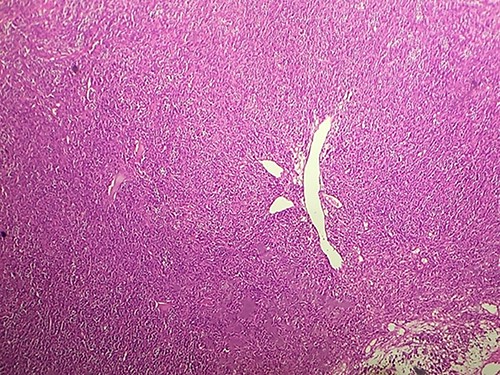

Macroscopically, the tumor was whitish, fleshy, firm, with a polylobed surface and harboring foci of necrosis. Histological examination showed densely cellular spindle cell proliferation without evidence of differentiation, with focal nuclear pleomorphism and few foci of tumor necrosis (<50%). Mitotic activity was high, estimated at 13 mitoses/10 fields at high power. (Figs 2–4) An exhaustive immunohistochemical study was necessary to classify this tumor (Cytokeratin AE1/AE3, Melan A, Epithelial Membrane Antigen (EMA), PS100, Smooth Muscle Actin (SMA), H-Caldesmone, Desmin, Myogenin, CD34, CD31, Chromogranin, Synaptophysin, CD56, P63, Beta-Catenin, STAT6 and SOX10). Tumor cells expressed SOX10 intensely and diffusely (Fig. 5), and PS100 focal (Fig. 6). The other markers were not expressed and the Ki 67 proliferation index was estimated at 60%.

HE section showing tumor cells pleomorphisme and mitotic figures (blue arrow) (x40).